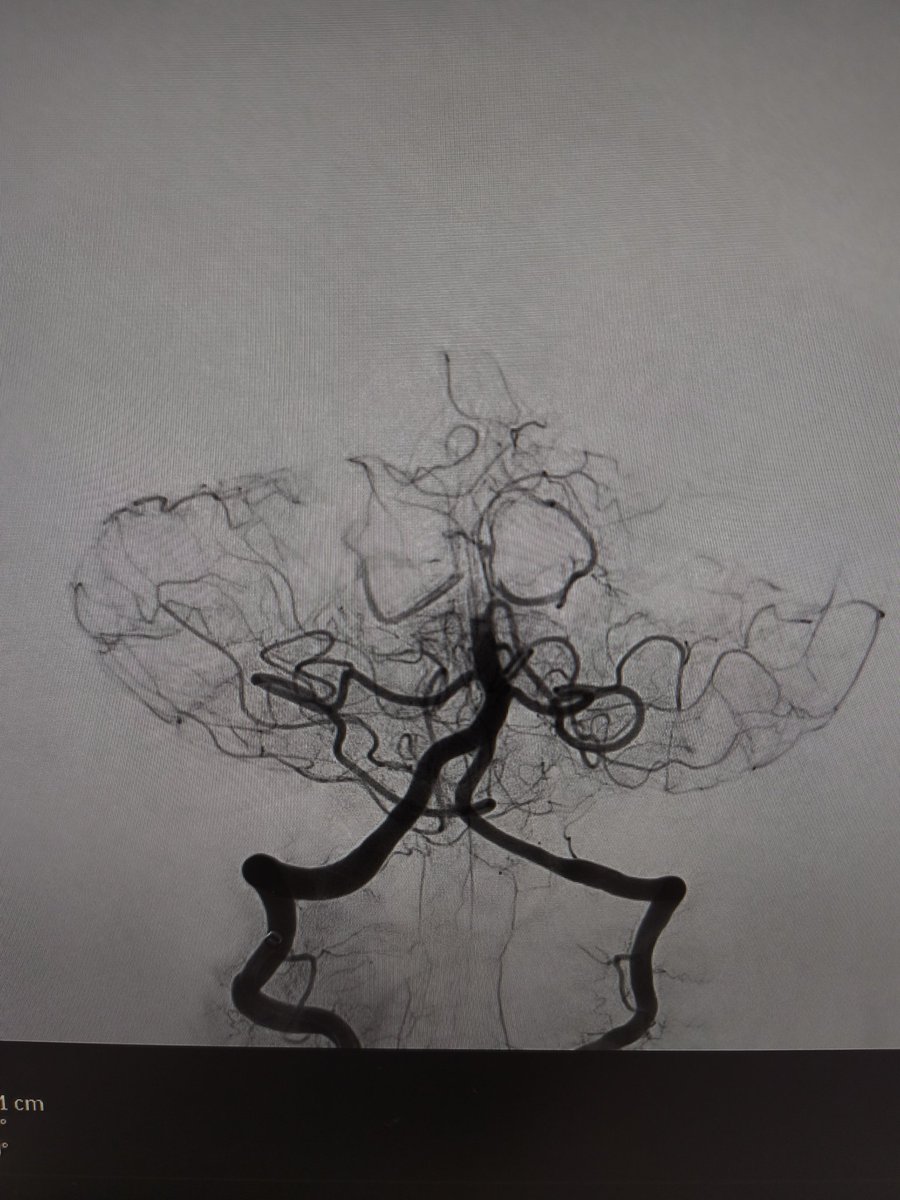

Distal M2 occlusion NiHSS 10. Complete recanalization using RED43 (@penumbrainc) aspiration catheter. NIHSS 2 at 24h.